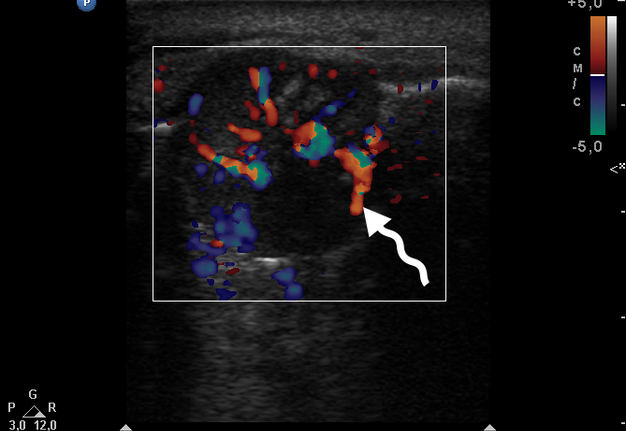

Color Doppler USG (Fig 5) showed prominent intralesional vascularity. Figure 6 demonstrates gray-scale USG of the lesion from two different angles, which allows for better visualization of echogenic areas (i.e., areas of ossification) within the lesion. It was not possible to adequately determine the area of the “stem” of the lesion.

During the complete surgical excision of the lesion (V.H.D.) followed by a peripheral osteotomy, profuse bleeding was noted both from the soft tissues and from the bone tissue of the alveolar ridge. This significant bleeding is confirmation of the color Doppler data on the presence of increased vascularization within the lesion.